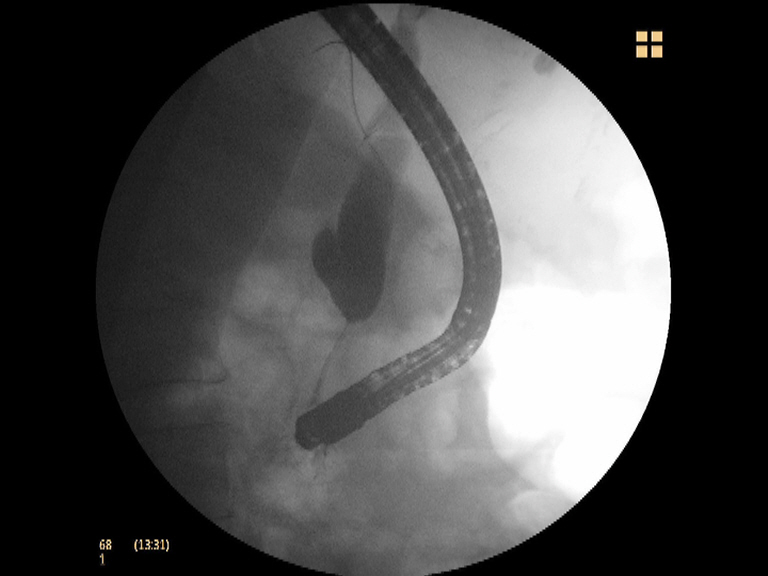

Ictericia obstructiva por cáncer de cabeza de páncreas: canulación con NK en un 2º tiempo y drenaje con prótesis metálica recubierta

Paciente de 74 años de edad con diagnóstico de neoplasia de cabeza pancreática irresecable tras realización de ECO, TAC abdominal USE-PAAF (estadio T3N3M0; IIIB) e ictericia obstructiva asociada. Se decide realizar drenaje con CPRE, usando varias técnicas de canulación de forma secuencial: canulación estándar, precorte con esfinterotomo de aguja asociado a una esfinterotomia transpancreática tipo 2, todas fallidas. Finalmente se decide demorar la técnica en unos días, consiguiendo la canulación de forma sencilla y drenando la vía biliar con una prótesis recubierta de 6 cm metálica (Wallflex biliar).